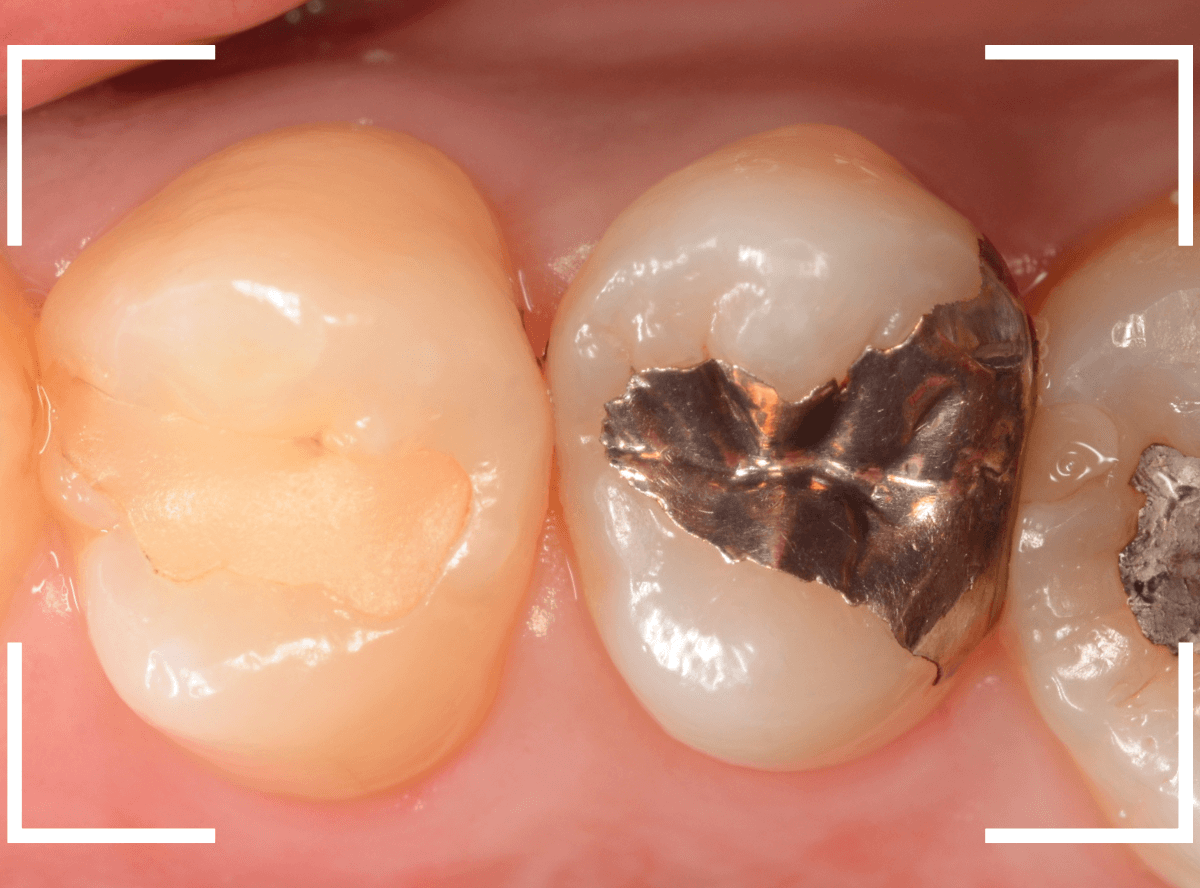

Case.13 奥歯の側面の虫歯

歯石除去中に、奥歯の側面の金属の部分が小さな虫歯になっているのが見つかった方です。

表面がうっすらと虫歯になっているように見えます、わかりますか?

レントゲン写真で確認します。

特に虫歯はなさそうに見えますが、側面の虫歯なので、虫歯が中で広がっている可能性も頭をよぎります。

麻酔をして慎重に虫歯を除去すると、中まで虫歯が広がっているのが確認できました。

患者さんに状況を説明して、つめものを外して中を確認します。

ある程度、虫歯を除去したところで、う蝕検知液でチェックします。

思ったよりも中まで虫歯が進行しているようです。

全ての虫歯を除去しました。

つめものの中で全体に虫歯が進行していました。